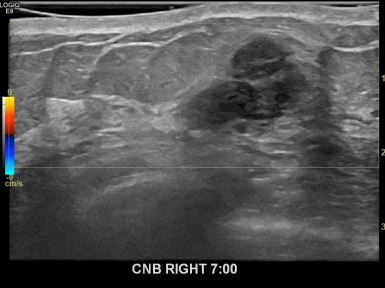

상기환자는 만져지는 멍울로 내원하신 50대후반

여성분으로 의심스러운 우측혹 조직검사 시행해 침윤성암 으로 진단되었습니다